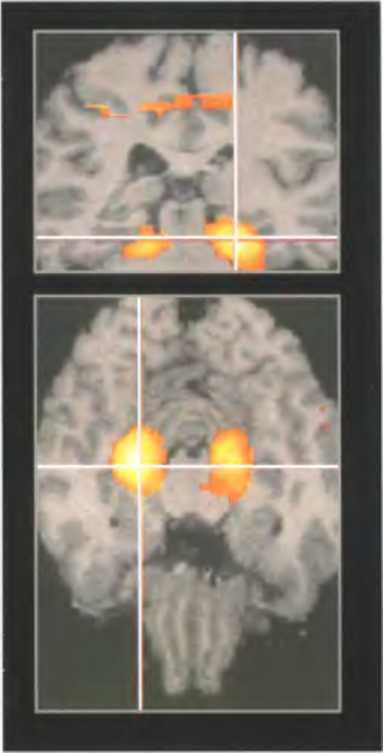

Активность в мозге человека, который смотрит фильм о том, как некто идет по городу, хорошо знакомому испытуемому. Светящаяся область — гиппокамп.

Гиппокамп обоих полушарий активируется, когда человека просят вспомнить какие-либо события, происходившие с ним самим, то есть обратиться к эпизодической памяти (вверху).

При ориентировании на знакомой местности гиппокамп тоже активируется, но только в правом полушарии (внизу).